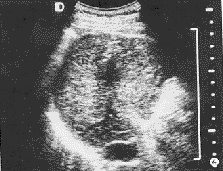

图3 治疗前肝右叶 5.3 cm×4.0 cm低回声肿块;

图4 图3同一病例治疗后肿块缩小呈强回声

例3,男性,64岁,肝硬化,肝内发现 5.3 cm×4.0 cm和 2.0 cm×3.0 cm 2个肿块,全身情况极差,中量腹水,出凝血时间、凝血酶原时间延长,血小板明显降低,合并大面积心梗,经利尿、输白蛋白、中药治疗2 d后,微波治疗3次,肿块缩小为 1.0 cm×2.0 cm强回声钙化区,境界不清,另一小肿块未显示,AFP正常。患者精神,食欲明显好转,无腹水(图3,4)。